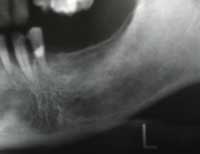

| 術前 | ソケットリフト手術 | 術後2年歯根周囲骨造成良好 |